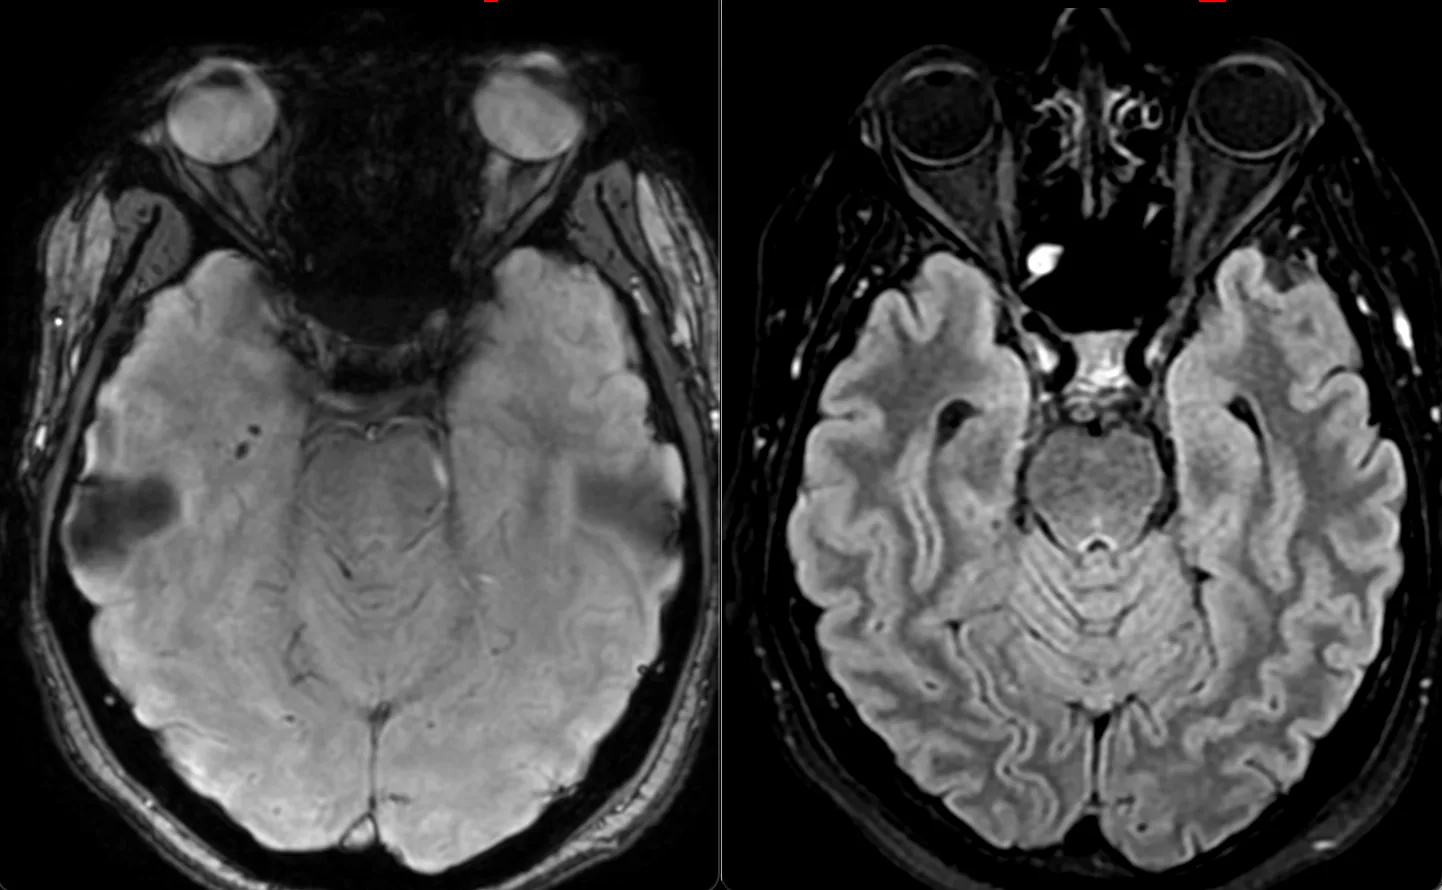

Женщина 32 года. Больной считает себя с 2024 г, когда стала отмечать онемение угла рта. Со слов пациентки ей был предварительно выставлен диагноз - РС, но дополнительных методов обследования и специфического лечения не проводилось. В настоящее время жалоб нет. В исследовании от октября 2024 отмечался очаг в левой затылочной доле с выраженным контрастированием, в настоящее время этот же очаг отмечается с сохраняющимся контрастированием. Формально - есть выполнение критериев диссеминации и в пространстве (юкстакортикальный и перивентрикулярный очаги есть), и во времени (есть усиливающиеся и неусиливающиеся очаги), клиника тоже вполне укладывается. Но! Найти в литературе подобных случаев мне не удалось, видел сам и максимум, что находил в литературе - полгода контрастирования. Получается, мы имеем дело с крайне атипичным рассеянным склерозом, или это не рассеянный склероз. А тогда что? Сосудистая мальформация не вариант - на SWI не видать. Какая-то ганглиоглиома? А другие очаги тогда что? Есть соображения? Кстати, диффузия стойко повышенная, и на б1000 почти не видно (изо). На Т2 не меняется